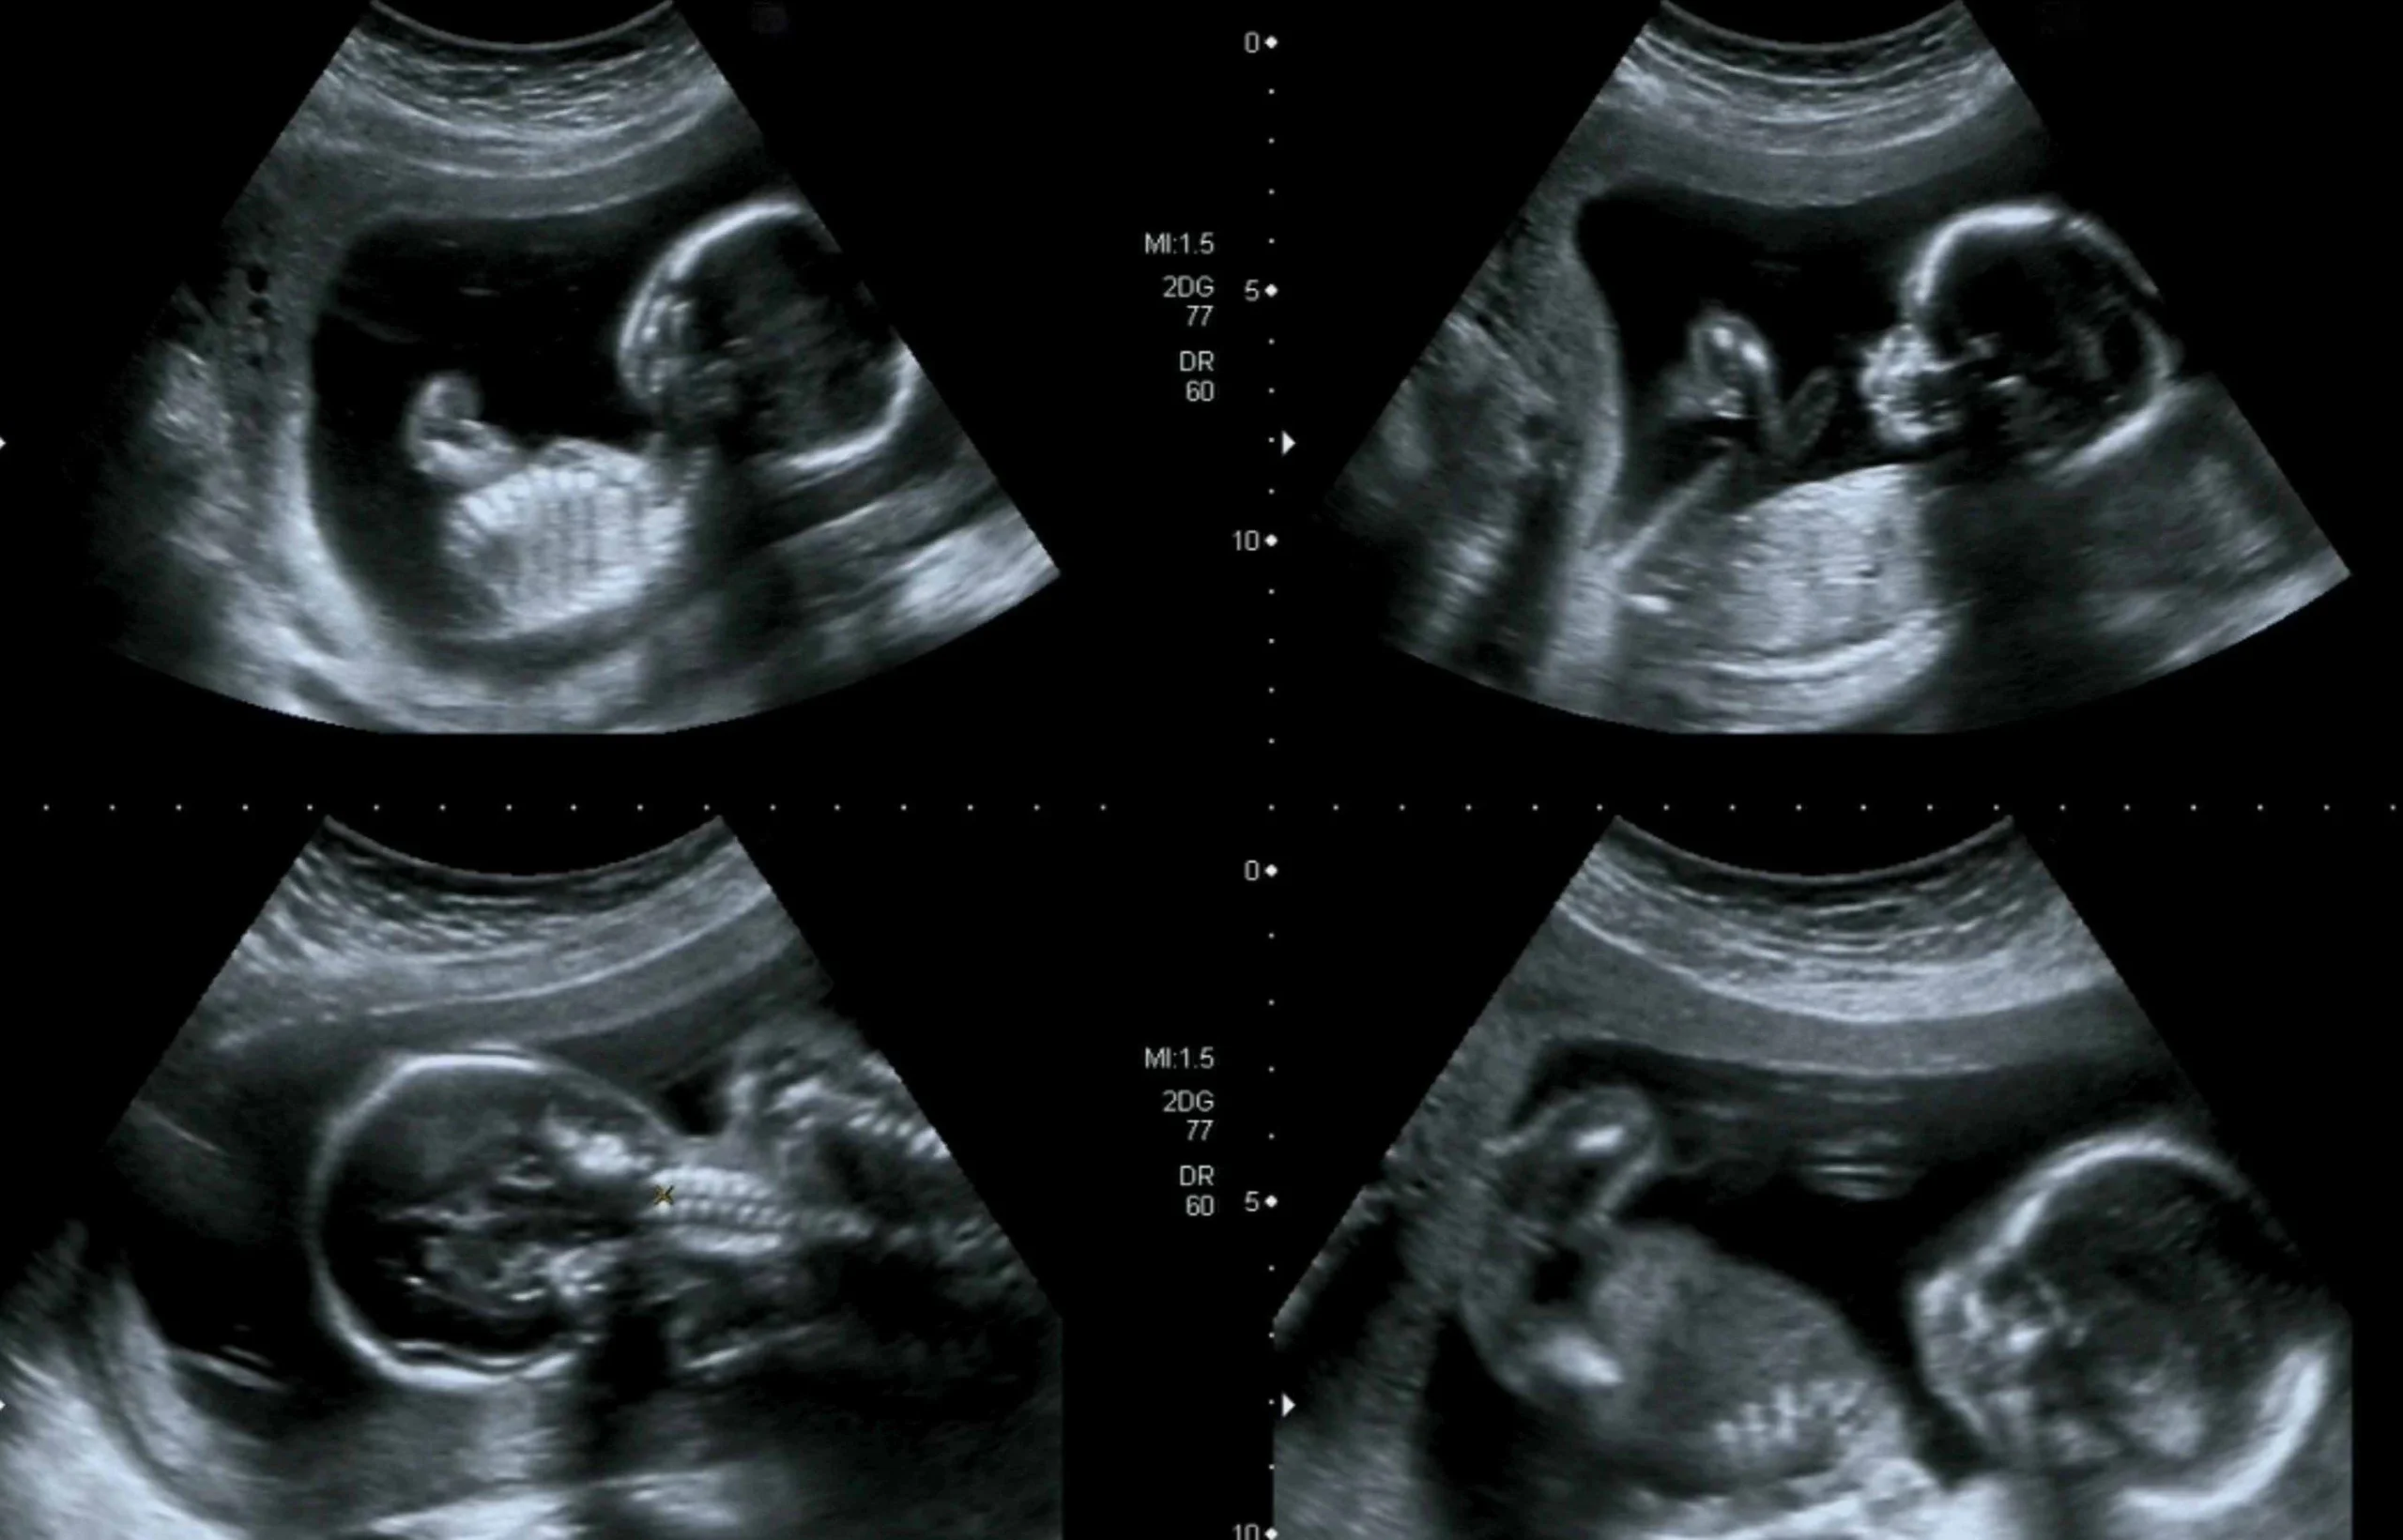

- Erhöhte Nackentransparenz (NT) im Ultraschall: Die Nackentransparenz ist die Flüssigkeit im Nackenbereich des Embryos. Eine erhöhte Nackentransparenz kann ein Hinweis auf eine Chromosomenstörung sein, insbesondere auf das Down-Syndrom.

- Nackentransparenzmessung im Ultraschall: Diese Untersuchung wird zwischen der 1und 1Schwangerschaftswoche durchgeführt.

- Ersttrimester-Screening: Diese Untersuchung beinhaltet die Nackentransparenzmessung und die Analyse bestimmter Blutwerte der Mutter.

Es gibt verschiedene Untersuchungen, die eine Chromosomenstörung feststellen können, z.B. Die Nackentransparenzmessung im Ultraschall, das Ersttrimester-Screening, der PraenaTest® und die Amniozentese.